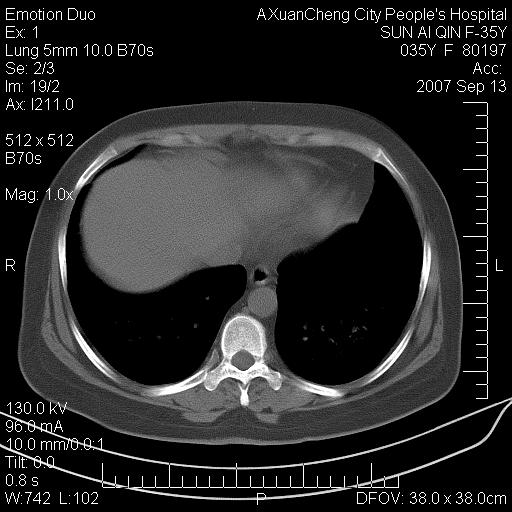

以下是引用天南地北在2007-9-13 13:43:00的发言:[br]考虑双肺、肺门侵润

以下是引用ydx_74在2007-9-13 15:42:00的发言:[br]仅看片,考虑右上肺癌并双肺转移,结合病史,考虑肺门、肺内淋巴侵润

以下是引用同在2007-9-13 15:08:00的发言:[br]支持肺门及双肺侵润.